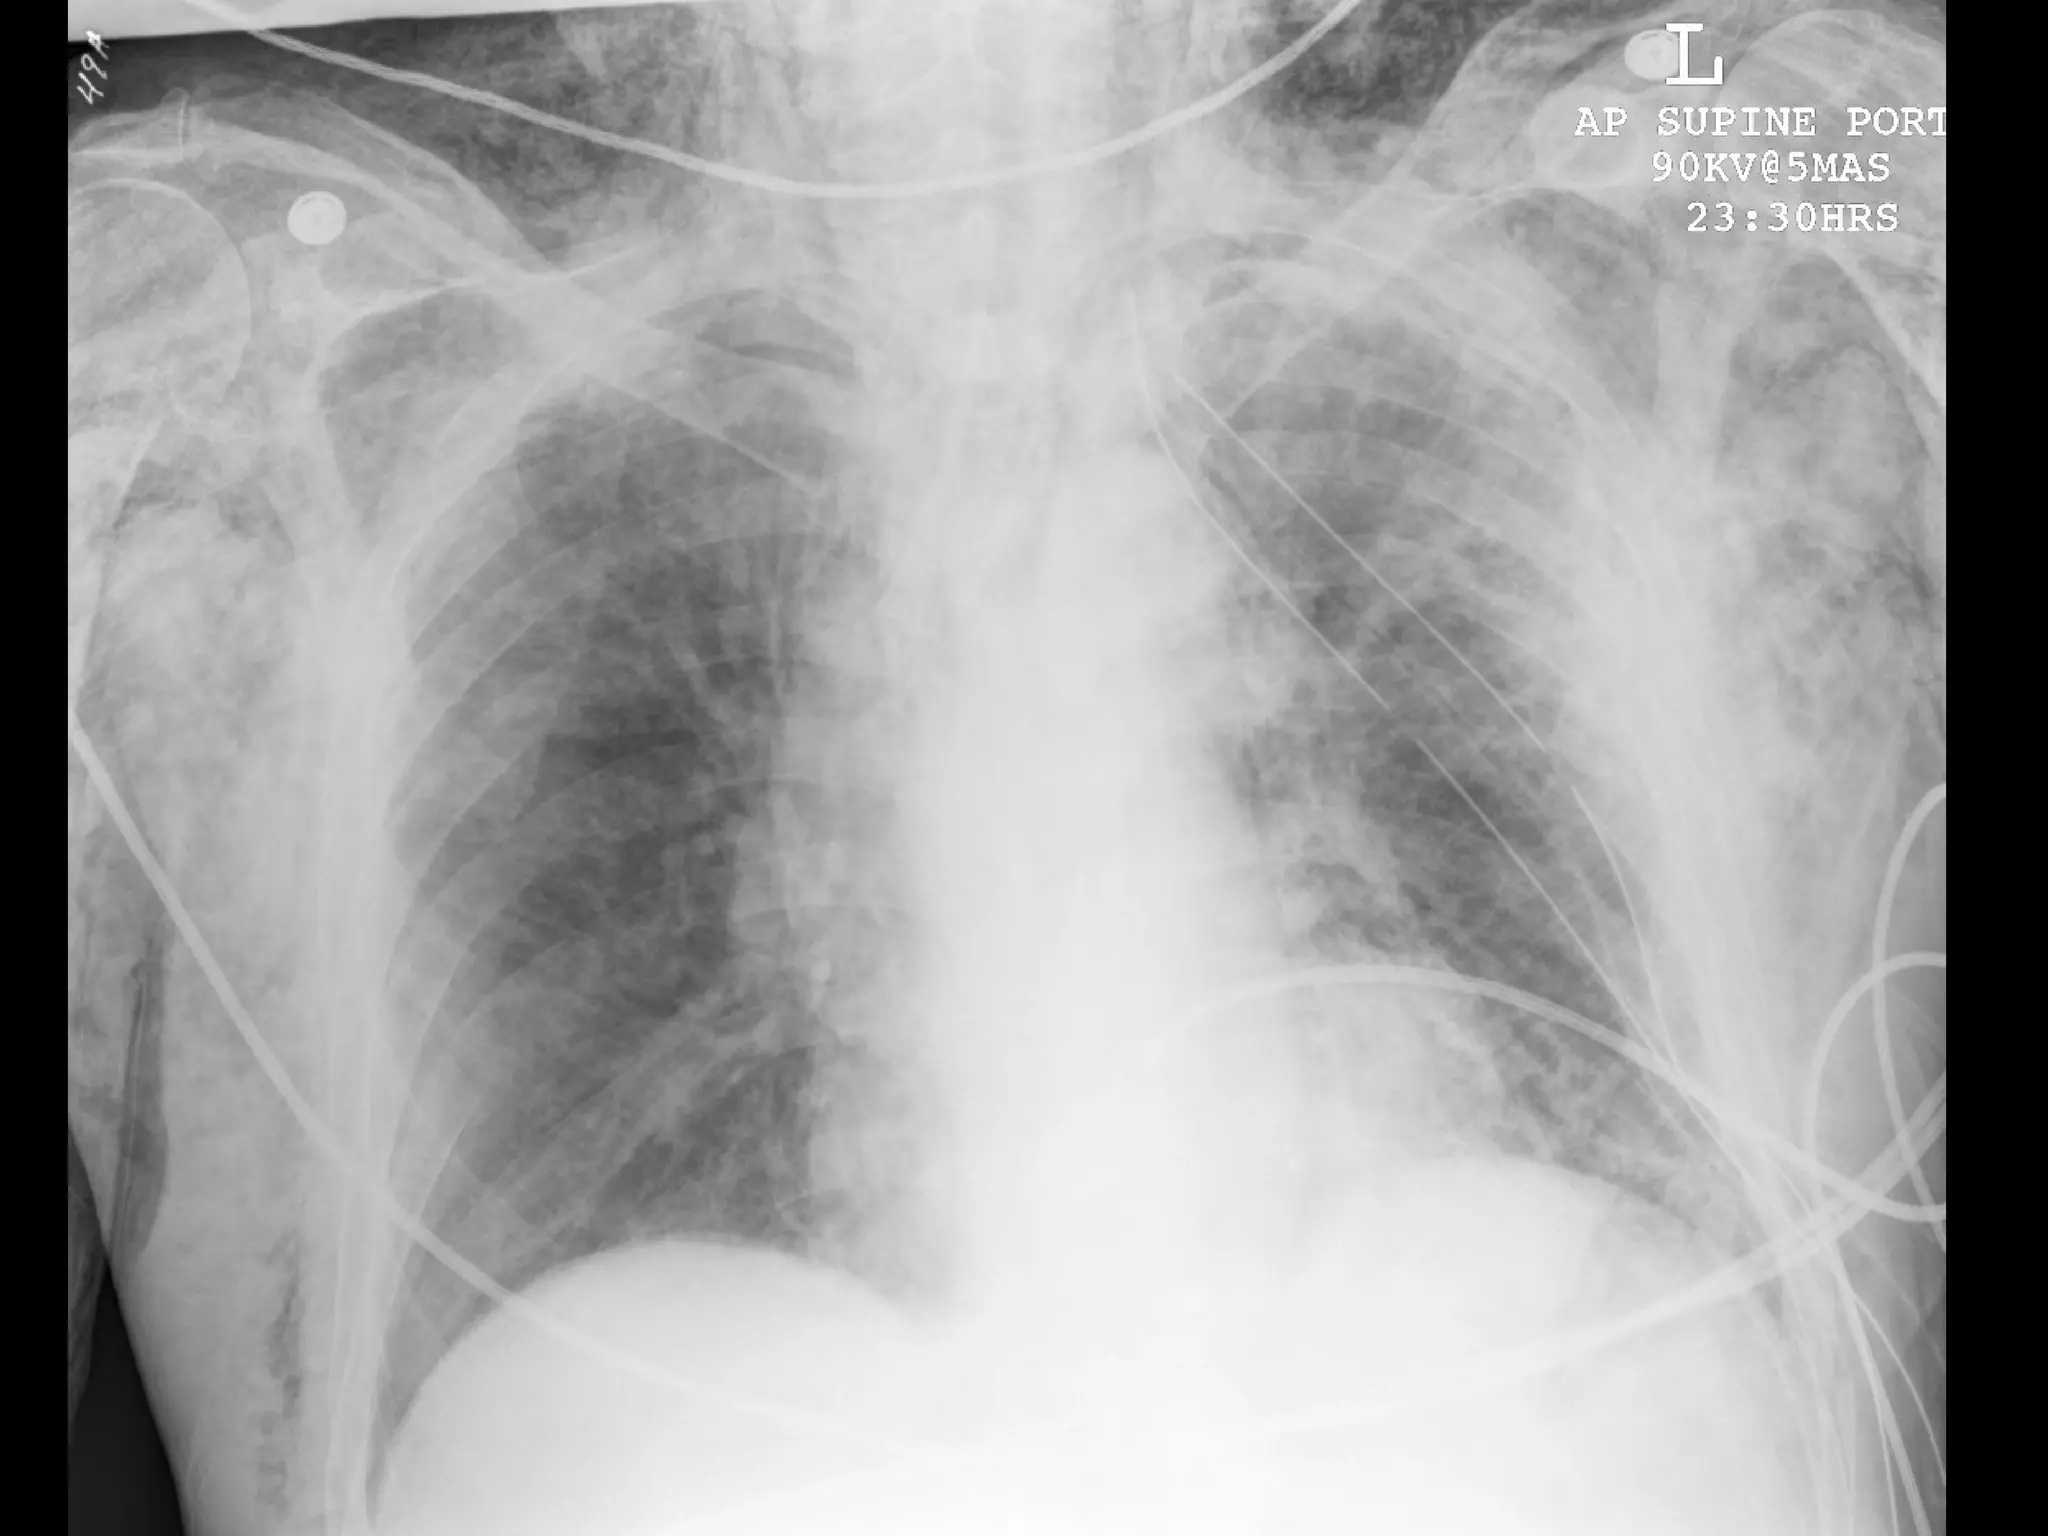

What’s Wrong With These Pictures?

What’s Wrong WithThese Pictures?

Chest tube inpoor position